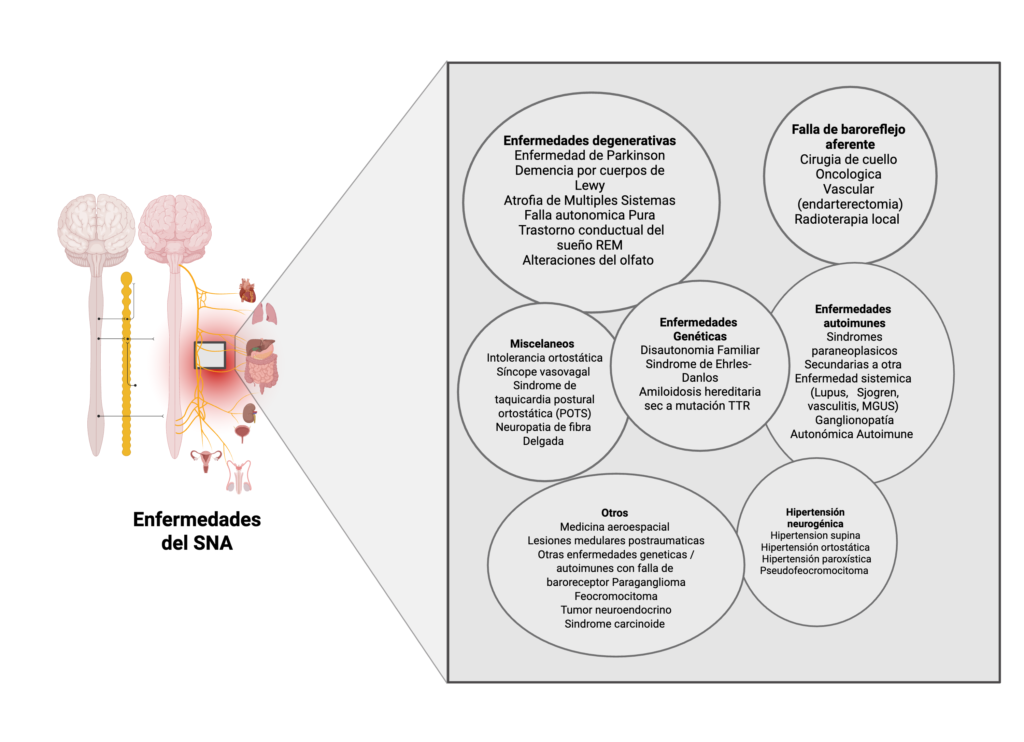

Prueba de mesa inclinada: ¿Por qué y cómo se realiza?

La prueba de la mesa inclinada es una herramienta clave para la evaluación de pacientes con disautonomía. Permite observar cómo responde el cuerpo a los cambios de posición, especialmente al pasar de la posición supina a una inclinación de 60 grados. La prueba simula los cambios que experimentan los barorreceptores al regular la presión arterial y la frecuencia cardíaca durante la bipedestación, reflejando situaciones de la vida real.

Esta prueba nos ayuda a comprender cómo el cuerpo gestiona funciones vitales como la circulación y la frecuencia cardíaca, lo cual es esencial para brindar una atención personalizada y segura

Tradicionalmente, la prueba de la mesa inclinada se realiza con el paciente en reposo, en un ambiente tranquilo y sin estímulos externos. Los avances en la comprensión de la fisiología han permitido refinar la técnica, convirtiéndola en una representación más precisa de las experiencias cotidianas.

Hemos incorporado el monitoreo avanzado de múltiples parámetros vitales durante la inclinación pasiva y activa, lo que proporciona datos individualizados de gran valor. Cada paciente es único, ya que las respuestas de los barorreceptores varían de una persona a otra.

La prueba de la mesa inclinada es una herramienta clave para la evaluación de pacientes con disautonomía. Permite observar cómo responde el cuerpo a los cambios de posición, especialmente al pasar de la posición supina a una inclinación de 60 grados. Algunos centros utilizan una inclinación de 70 grados. Esta posición alcanza aproximadamente 0.94 unidades G y desafía la función de los barorreceptores, que regulan la presión arterial y la frecuencia del pulso durante la postura erguida, reflejando situaciones de la vida real.

La prueba de la mesa inclinada ayuda a comprender cómo el sistema nervioso simpático gestiona funciones vitales como la circulación y la frecuencia cardíaca, lo cual es esencial para brindar una atención personalizada y segura.

Monitoreo Electroencefalográfico

Un electroencefalograma (EEG) registra la actividad eléctrica del cerebro mediante electrodos colocados en el cuero cabelludo. Evalúa la función cerebral y detecta posibles alteraciones en la actividad eléctrica.

El mapeo cerebral es una técnica avanzada que analiza la actividad eléctrica en diferentes regiones del cerebro con mayor detalle. Permite visualizar patrones anormales y detectar alteraciones durante la vigilia y el sueño, orientando el diagnóstico y el seguimiento de pacientes con sospecha de epilepsia o ayudando a confirmar crisis no epilépticas funcionales en pacientes con trastornos neurológicos funcionales (TNF)